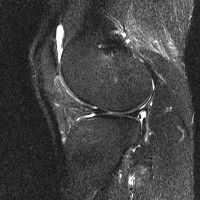

무릎 mri 간단히 봐주실 수 있으시나요 ㅠㅠ

안녕하세요 8년전 십자인대 수술하고 최근 무리한 운동에 무릎 불편감이 생겨서

mri 찍었습니다.

진단결과는 첫 찍은 병원에서 활액막염 이라는 진단을 받았습니다. 혹시 봐주실 수 있으실까요?

• 안녕하세요. 강성주 의사입니다.

올라온 MRI가 단편적이라서 정확한 진단에 어려움이 있지만 십자인대에는 큰 이상이 있지는 않은것 같으며, 무릎관절내 물이 있는 것으로 보아 활액막염의 진단이 맞을 것 같습니다.

하지만 단편적인 영상이기 때문에 촬영병원에서 정확한 판독지 등을 받으시는 것이 좋겠습니다.